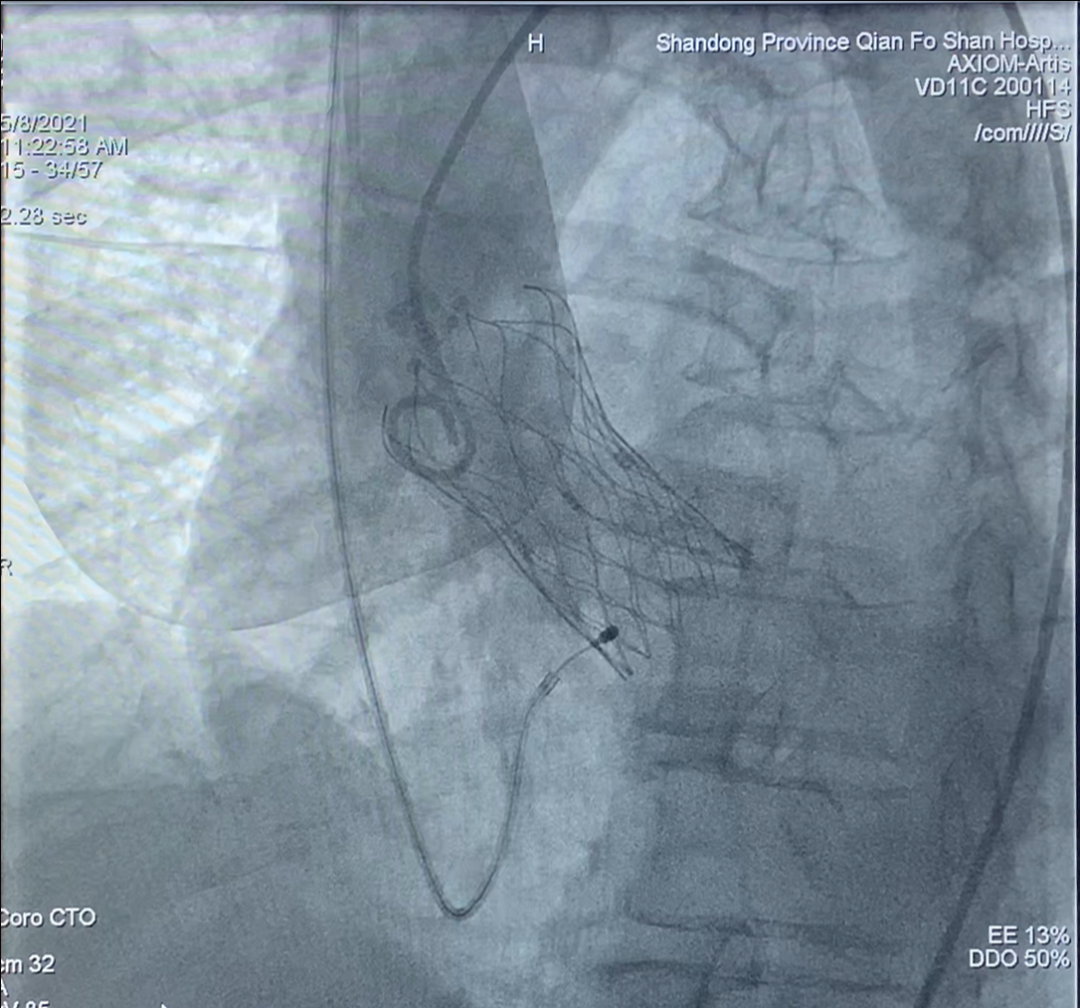

2. 迅速送入Vitaflow27mm人工瓣膜至主动脉瓣释放位置,尝试调整人工瓣膜与主动脉瓣同轴,进行释放。

3. 释放瓣膜成功,位置良好,形态理想,瓣叶开闭正常,流速正常,未见瓣周漏。